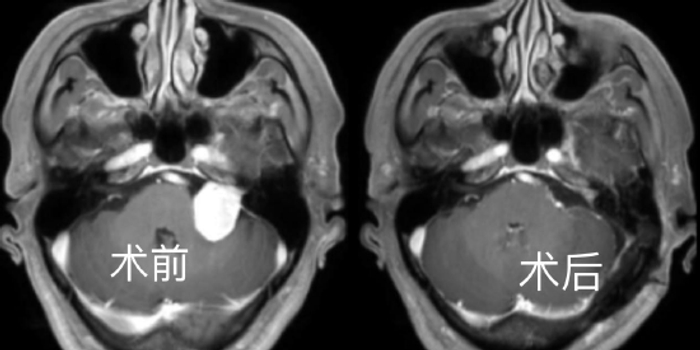

患者是44岁的李师傅,来之湖北红安县的工人,前2年发现听力下降,伴有耳鸣,当时未予以重视。就诊当地医院发现巨大右侧囊实性听神经瘤,大小约4*3.3*4.2cm。肿瘤压迫控制呼吸、心跳的“生命中枢”脑干,后来出现右侧肢体无力,右侧肢体肌力约4级。近日住入该院后,神经疾病诊疗中心王煜教授,神外金胜昔教授团队科学论证手术方案,再麻醉科胡玲教授团队精心护航下,历经7小时完整切除肿瘤,术后恢复良好,术后病理证实为听神经鞘瘤。